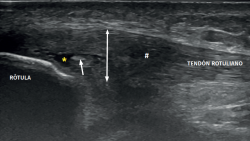

El estudio ecográfico de un tendón lesionado mostrará imágenes con hipoecogenicidad y pérdida del patrón fibrilar, aparición de tejido conectivo desorganizado y engrosamiento del tendón (Figura 3). En ocasiones, encontraremos imágenes hipoecoicas bien delimitadas, indicativas de roturas intrasustancia de formas nodulares o fibrilares, de presentación habitual en la región más profunda del tendón en el polo inferior contiguo a la rótula (Figura 4).

En la porción media del tendón se puede observar engrosamiento (> 3,5 mm), asociado a áreas hipoecoicas con zonas de desorganización del colágeno y perdida del patrón fibrilar.

Figura 4. Tendinopatía rotuliana estudiada con ecografía de alta definición. Sonda lineal en visión longitudinal. La doble flecha muestra un tendón engrosado con zonas de alteración del patrón fibrilar hipoecogénicas (#), rotura intrasustancia (asterisco), así como fibrosis (flecha).